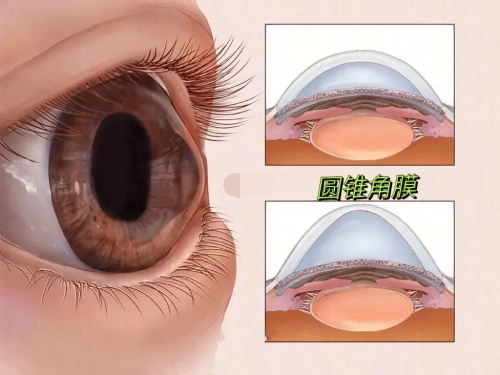

白内障是一种常见的眼部疾病,通常会导致视力模糊、眼睛敏感等症状。